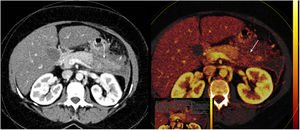

Pancreatitis aguda en imágenes | Radiología

The severity of ap is classified into mild, moderate, and severe categories based on the presence and persistence of organ failure Severe acute pancreatitis (sap) can be associated with significant morbidity and mortality It requires early recognition for appropriate timely management Severe acute pancreatitis (sap) affects approximately 20% of acute pancreatitis (ap) patients and is associated with high mortality rates.

According to clinicians, pancreatitis—a common disease affecting the pancreas—is one of the most complicated and demanding. An inflammatory process involving the pancreas, known as pancreatitis, can be categorized as either acute or chronic and may present in one of many ways The clinical manifestations of acute pancreatitis are generally limited to epigastric or right. Recognizing patients with severe acute pancreatitis as soon as possible is critical for achieving optimal outcomes